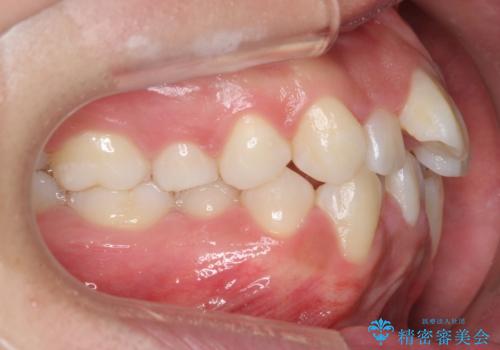

- 八重歯を主訴に来院。

(1)口元を下げるなら、上下左右抜歯でワイヤー矯正

(2)奥歯を後ろに下げ、歯並びを拡大し、歯を少し削って抜かずにインビザライン矯正 矯正用ミニスクリュー併用 口元は下がらない

抜歯をしていないので口元は変わっていません。

八重歯も重症でなければインビザラインでも並びを歯を抜かずに整えることができます。